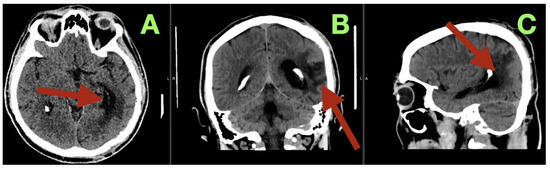

Background/Objectives: Arteriovenous malformations (AVMs) in the dominant temporo-parieto-occipital (TPO) junction of the brain are extremely rare and very difficult to remove surgically because this area includes multiple sensory and language networks. Due to the fact that many patients present with bleeding, surgeons have to find a delicate balance between removing all of the AVM tissue and preserving the functional areas of the brain where important functions occur. This study is reporting a case demonstrating how precise clinical–radiologic correlation, detailed anatomical knowledge, and deliberate microsurgical techniques can allow safe removal of the AVM and improve the patient’s neurologic function without the need for additional intraoperative technology. Case Presentation: A 47-year-old right-handed male patient experienced persistent neurological deficits after experiencing a hemorrhage from an AVM in his dominant posterior hemisphere, which included mild language difficulties, right hemifacial–brachial spasticity, parietal sensory loss and a visual field defect of his right eye known as an inferior quadrantanopia localized to the TPO junction. Cerebral angiography identified a small, compact, high-flow AVM (40 × 30 mm) fed by distal branches of the middle cerebral artery (M4), posterior cerebral artery (P4), anterior cerebral artery (A4), as well as a small branch of the superior cerebellar artery (SCA). Blood drained into two veins of the Trolard and Labbé. The authors removed the AVM completely by circumferential dissection of the nidus along gliotic planes using a microscope. Feeders were then sequentially disconnected, and the venous outflow was preserved until the AVM could be removed en bloc. Post-operative angiograms demonstrated complete removal of the AVM with normalization of blood flow to the surrounding cortex. The patient’s neurologic function improved over time and at three months post-operatively, he was functioning independently (modified Rankin Scale = 1; Barthel Index = 100) and there was no evidence of residual nidus or edema on imaging. Conclusions: High-flow AVMs in the dominant TPO junction can be completely removed using a disciplined microsurgical approach and a feeder first/vein last disconnection method based on anatomy. The patient’s improvement in function represented reperfusion and reintegration of an injured but still functional network of the brain, reinforcing the idea that careful observation, a deep understanding of brain anatomy, and restrained surgical technique are critical to achieving long-term results in AVM surgery. Full article

Figure 1